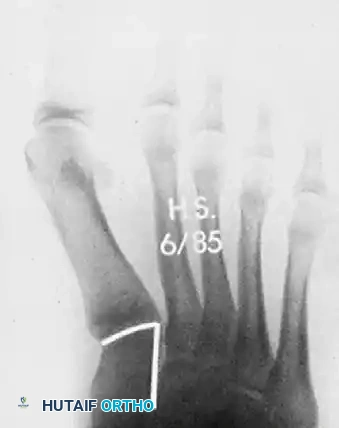

الصور التالية توضح حالة لمريض مراهق يعاني من انحراف شديد، وكيف تم التعامل معها جراحياً ومتابعتها